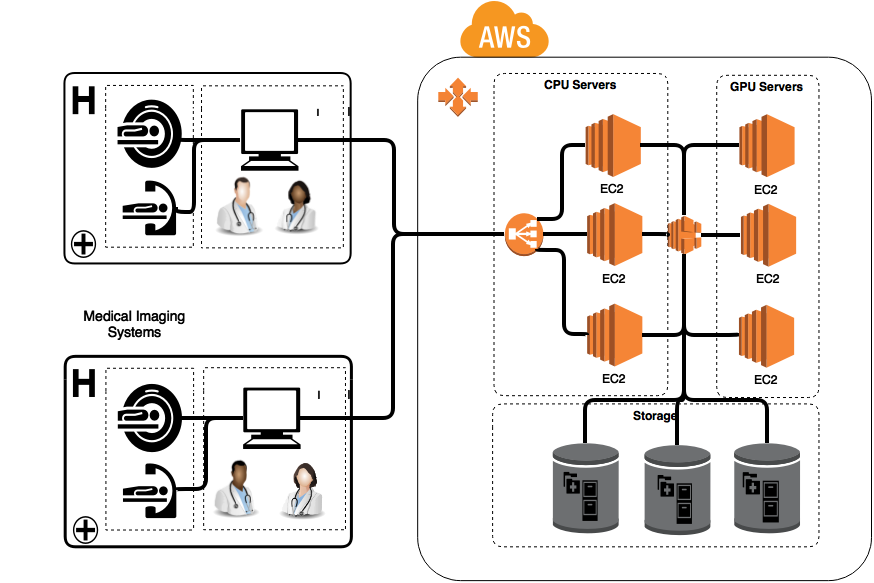

How Behold.ai Uses AWS to Do It

Behold.ai is architected to handle High Performance Computing (HPC) requirements while providing a HIPAA-compliant service. We harness the massive parallelism of high-performance GPUs hosted on AWS to speed up the process. Advances in GPGPU programming enable us to have a very deep convolutional network with hundreds of millions of parameters. This must all be done while strictly adhering to the privacy rules of HIPAA/HITECH. We were drawn by the leading-edge, security-oriented services and responsive expert support offered by AWS, which allow us to provide our clients with rock-solid patient data security.

We rely on a range of AWS services to keep our infrastructure running smoothly and the patient data safe:

- Amazon EC2 — EC2 provides the compute resources needed to run our backend service. Its elastic nature enables us to scale rapidly in response to requirements in computing resources. AWS is able to support our compute and memory-intensive algorithm requirements through its GPU instances, whose massively parallel capabilities and energy efficiency makes them state-of-the-art in training deep neural networks.

- Elastic Load Balancing (ELB) — ELB automatically distributes incoming web traffic across our EC2-backed web servers.

- Elastic Block Store (EBS) — EBS provides persistent, highly available, fault tolerant block level storage for the image data. EBS encryption provides a secure means to store patient data at rest. Data is stored in low-latency SSD and provisioned IOPS SSD, allowing for I/O performance. The elasticity of EBS allows us to scale block storage as needed.

We use additional AWS security features to ensure that our services are impenetrable. For example, Identity and Access Management (IAM) enables us to use security groups to control access to our services and resources. We use encryption to ensure that data is transmitted securely to our servers.

As shown in the following architecture diagram, we use AWS to integrate with clinics and hospital systems though an unobtrusive workflow in order to help a radiologist make an informed decision.

After a patient has scans taken at a medical imaging center, the scans are sent to Behold.ai’s servers for real-time analysis. The images are then immediately sent back to the radiologist along with tags listing the ailments identified by Behold.ai’s pre-trained models. Radiologists then verify the suggestions and may accept or reject them. Behold.ai takes this feedback and retrains its models, therefore learning over time.